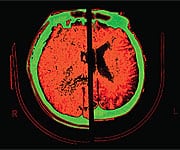

Alzheimer’s Destroys Memory in Multiple WaysWhile scientists have not yet been able to pinpoint the exact cause of Alzheimer’s, they have been able to elucidate some of the biochemical processes that produce the hallmark mental changes characteristic of the disease. First, Alzheimer’s involves a significant decline in brain levels of acetylcholine, a neurochemical that is vitally important for memory formation and retention. Second, the disease is accompanied by an accumulation of harmful amyloid-beta deposits, or senile plaques, in the brain. Third, brain autopsies of Alzheimer’s patients show evidence of substantial oxidative damage wrought by free radicals. When energy is generated, free radicals are produced in every cell in the body, particularly brain cells; however, in Alzheimer’s disease, free radicals are produced in much greater amounts then normal, leading to significant damage to the brain. In a recent article on this topic in the Annals of the New York Academy of Sciences, the investigators concluded that “altogether, our findings emphasize the importance of . . . oxidative stress in the pathogenesis of [Alzheimer’s disease].” 5 Deadly Connections: Hypoxia, Amyloid-Beta, and Oxidative StressWhile researchers certainly know much more today about how Alzheimer’s affects the brain, we still do not know why this disease afflicts some people and spares others. However, groundbreaking research strongly suggests an intimate link between Alzheimer’s and cardiovascular diseases such as atherosclerosis, hypertension, and stroke. A recent report in the Proceedings of the New York Academy of Sciences has shown that hypoxia—the reduction in oxygen received by the brain due to decreased blood flow—may be a “trigger” that contributes to the pathogenesis of Alzheimer’s disease.7 The authors of this important research have shown that hypoxia increases the activity of a gene called BACE1, which is involved in the production of damaging amyloid-beta plaques found in the brains of Alzheimer’s patients. The researchers found that hypoxia markedly increased amyloid-beta deposition and plaque formation in central neurons. Since a decrease in the amount of oxygen delivered to the brain may very well set off a cascade of events that culminates in Alzheimer’s disease, conditions like heart disease—a cause of brain hypoxia—provide a stark connection between heart disease and Alzheimer’s. Besides increasing amyloid-beta production, hypoxic conditions in the brain also heighten levels of oxidative stress, an increase that poses serious dangers for the delicate cells of the central nervous system. Scientists believe that chronic oxidative stress may cause neuronal cell death, which ultimately manifests as the cognitive impairment and brain pathology known as Alzheimer’s disease.8 Finally, hypoxia caused by heart disease may also contribute to the lower levels of acetylcholine observed in Alzheimer’s disease.